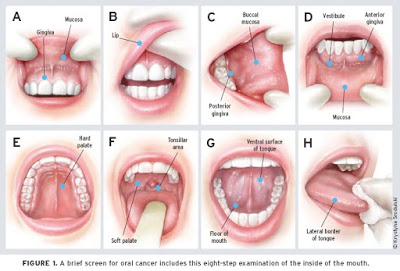

Η συχνότερη θέση εντόπισης του καρκίνου του στόματος είναι η γλώσσα με ποσοστό 40%. Οι καρκίνοι της γλώσσας εντοπίζονται συχνότερα στη οπίσθια- πλάγια περιοχή και στην κοιλιακή επιφάνεια. Η 2η σε συχνότητα θέση εντόπισης είναι το έδαφος του στόματος. Λιγότερο συχνές θέσεις εντόπισης είναι τα ούλα, ο παρειακός βλεννογόνος, τα χείλη και η σκληρή υπερώα.

Καρκίνος στόματος – Συμβουλές για την υγεία: Η αυτοεξέταση

Μία φορά τον μήνα συνιστάται να εξετάζουμε μόνοι μας την περιοχή του στόματος. Για τον λόγο αυτό, διαλέξτε ένα σημείο με καλό φωτισμό μπροστά σε έναν καθρέφτη. Για την εξέταση θα χρειαστείτε μια αποστειρωμένη γάζα, που μπορείτε να προμηθευτείτε από ένα φαρμακείο. Με τη βοήθεια δύο δακτύλων, του δείκτη και του αντίχειρα, ανασηκώστε τα χείλη, παρατηρήστε το χρώμα και τη σύστασή τους και ψηλαφίστε το εσωτερικό τους. Επαναλάβετε τη διαδικασία αυτή για τα ούλα, τις παρειές και την υπερώα. Στη συνέχεια παρατηρήστε τη γλώσσα.